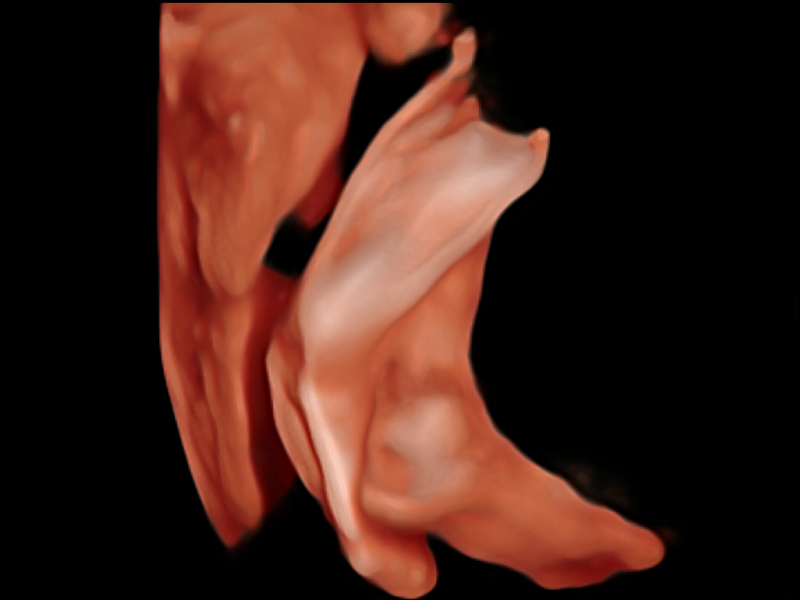

临床图像